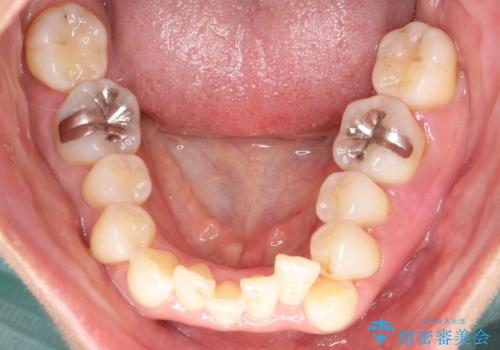

重度のガタガタのインビザラインによる非抜歯矯正

- 上下の歯のガタガタを主訴に来院されました。

インビザラインで奥歯を後方に移動させるのと、歯と歯の間をわずかに削ることでスペースを作り、歯を並べる計画としました。